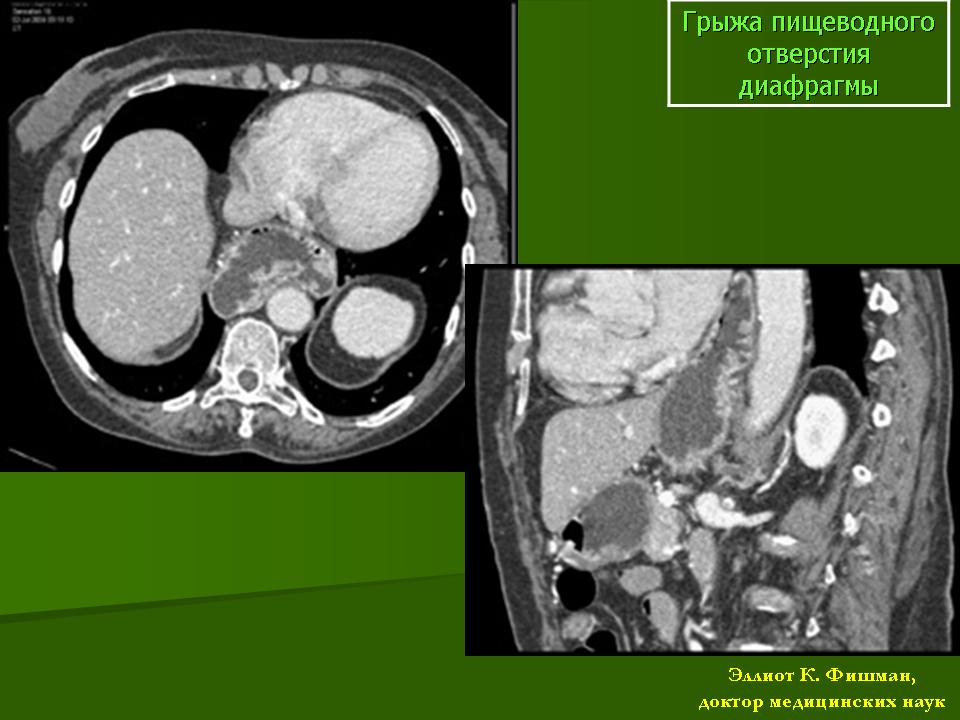

Грыжи пищеводного отверстия диафрагмы

Грыжи пищеводного отверстия диафрагмы могут иметь как врожденный, так и приобретенный характер. Врожденные грыжи в детском возрасте являются пороками эмбрионального развития пищеварительной системы и могут приводить к формированию врожденных стриктур. Приобретенные грыжи пищеводного отверстия развиваются преимущественно у взрослых, часто встречаются у больных, перенесших операции на желудке, страдающих эзофагоспазмом, язвенной болезнью, энтеритом. Современная классификация грыж пищеводного отверстия построена с учетом морфологических и клинических дан­ных, этиологии, патогенеза и сопутствующих заболеваний:

Рентгенологическое исследование  при подозрении на грыжу пи­щеводного отверстия необходимо начинать с обзорной рентгеноскопии грудной клетки и брюшной полости в вертикальном положении пациента в различных проекциях. Особое внимание необходимо обращать на срединную тень и область переднего отдела заднего средостения, положение, форму и размеры газового пузыря же­лудка. При наличии фиксированной грыжи на фоне переднего отдела заднего средостения может определяться горизонтальный уровень жидкости или дополнительная тень, форма которой ме­няется в процессе исследования.

После этого переходят к рентгеноконтрастному исследованию с жидкой бариевой взвесью в обычных проекциях с изучением пи­щеводно-желудочного перехода. Для выявления грыжи пищеводного отверстия  исследование проводят в горизонтальном положении на животе с поворотом в левое косое положение, на вдохе и выдохе, во время тугого за­полнения пищеводно-желудочного перехода.

Аксиальные нефиксированные грыжи пищеводного отверстия встречаются наиболее часто. Среди аксиальных грыж различают: - кардиальные грыжи, при которых в грудную полость, кроме абдоминального сегмента пищевода, смещается анатомическая кардия с частью кардиального отдела же­лудка; – кардиофундальные грыжи, когда перемещается не толь­ко кардия, но и свод (дно) желудка; - субтотальные и тотальные грыжи, при которых перемещается через пищеводное отверстие перемещается большая часть желудка или весь желудок без укорочения пищевода.

Рентгенологически при прохождении первого глотка жидкой бариевой взвеси, в большинстве случаев, выявляется более широкий, чем в норме, пищеводно-желудочный переход, что является одним из призна­ков эзофагита. В других случаях определяется чрезмерно длин­ный и извитой абдоминальный сегмент пищевода, наличие изме­ненных складок слизистой оболочки.  Могут также выявляться изменения со стороны желудочного пузыря: уменьшение в раз­мерах и деформация, дополнительная тень с волнистыми очерта­ниями в проекции кардии за счет отечных складок, рефлюкс со­держимого желудка в пищевод. При выявлении этих косвенных симптомов необходимо дополнительно провести исследования в горизонтальном положении на животе с поворотом в левое лопаточное положение, так как в этом положении хорошо виден почти весь пищевод и верхний отдел желудка. При средних и больших грыжах один глоток жидкой бариевой взвеси позволяет определить, что абдоминальный сег­мент пищевода, кардия и кардиальная часть, а также другие от­делы желудка расположены над диафрагмой, выявляются грыжевые ворота и наличие в их области более трех желудочных складок.